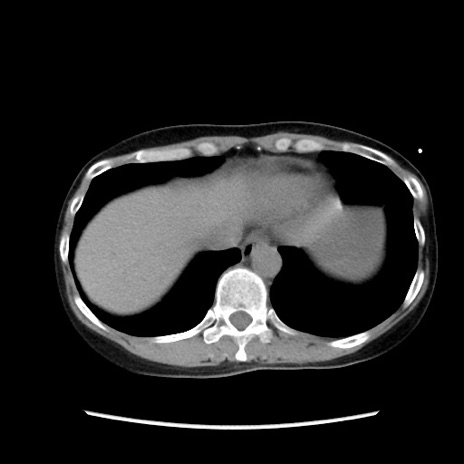

症例32(横断像)

【症例】40歳代 女性

【主訴】上腹部痛、嘔気・嘔吐

【現病歴】約9時間前頃から急に上腹部痛、嘔気、嘔吐が出現。改善しないため救急要請。

【既往歴】子宮頚癌(広汎子宮全摘術、放射線療法)、腸閉塞

【身体所見】腹部:平坦、軟、腸雑音亢進、上腹部を中心に腹部全体に圧痛あり。

【データ】WBC 8400、CRP 0.03